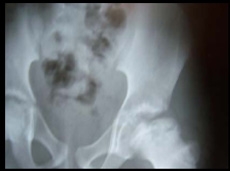

Conducted CME’s, OPD’s & Surgeries at various Hospitals in Ethiopia |

Conducted CME's, OPD's & Surgeries at various Hospitals in Ethiopia-2011